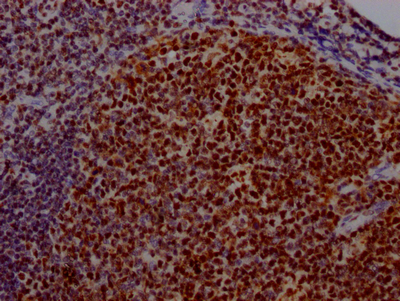

IHC image of CSB-RA192026A0HU diluted at 1:100 and staining in paraffin-embedded human prostate cancer performed on a Leica BondTM system. After dewaxing and hydration, antigen retrieval was mediated by high pressure in a citrate buffer (pH 6.0). Section was blocked with 10% normal goat serum 30min at RT. Then primary antibody (1% BSA) was incubated at 4℃ overnight. The primary is detected by a Goat anti-rabbit IgG polymer labeled by HRP and visualized using 0.05% DAB.

CSB-RA192026A0HU

IHC image of CSB-RA192026A0HU diluted at 1:100 and staining in paraffin-embedded human tonsil tissue performed on a Leica BondTM system. After dewaxing and hydration, antigen retrieval was mediated by high pressure in a citrate buffer (pH 6.0). Section was blocked with 10% normal goat serum 30min at RT. Then primary antibody (1% BSA) was incubated at 4℃ overnight. The primary is detected by a Goat anti-rabbit IgG polymer labeled by HRP and visualized using 0.05% DAB.